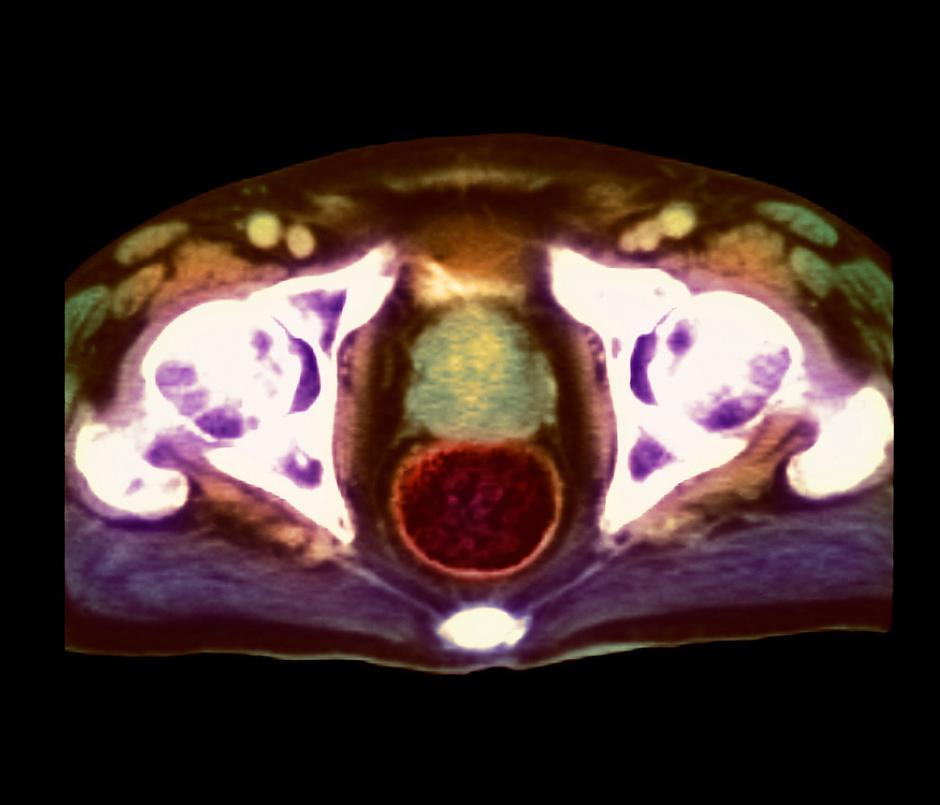

Najpogostejši rak pri moških: Na leto ga v Sloveniji diagnosticirajo pri okrog 1600 moških, 400 jih umre. Pri tistih, ki redno uživajo mlečne izdelke, za 65 odstotkov večja verjetnost za raka prostate.

Mleko in mlečni izdelki povečujejo tveganje za raka prostate, je pokazala velika študija, objavljena v reviji Ameriškega združenja za osteopatijo. (Journal of the American Osteopathic Association).

Tako imenovana metaanaliza navaja izsledke 47 raziskav nastalih med letoma 2006 in 2017, v katerih je sodelovalo dober milijon ljudi. "Moški, ki pojedo veliko mlečnih izdelkov imajo do 65 odstotkov večjo verjetnost da bodo zboleli za rakom prostate," ugotavljajo.

Skupina avtorjev je ob tem našla pozitivno povezavo med rastlinsko hrano in rakom, povezanosti med tveganjem za nastanek raka prostate in drugo živalsko hrano, vključno z rdečim, belim in predelanim mesom ter ribami, pa niso ugotovili. "V naši raziskavi izpostavljamo zaskrbljenost zaradi prevelike porabe mlečnih izdelkov," pravi John Shin, onkolog na kliniki Mayo, ki je glavni avtor te študije. Po njegovem je vse več dokazov o "koristnosti uživanja rastlinske hrane."

Najpogostejši rak pri moških

Na leto v Sloveniji odkrijejo okoli 1600 novih primerov, večinoma pri starejših, zaradi posledic raka prostate pa letno umre okoli 400 moških.